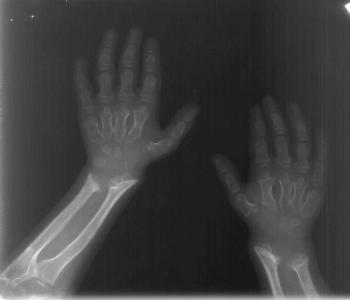

Male child of normal intelligence sent for skeletal survey for coarse facial features, short stature and spinal deformity.